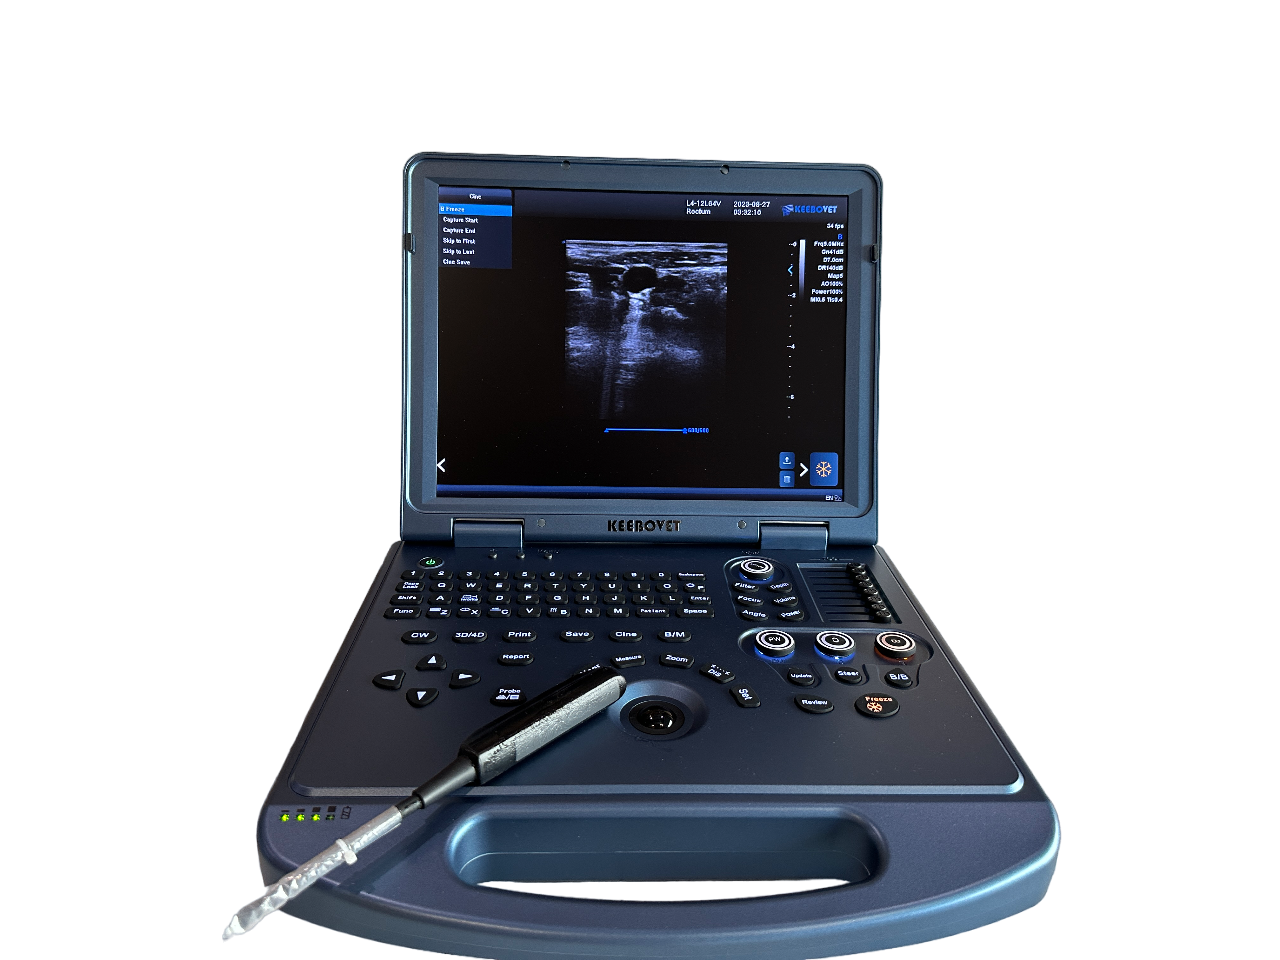

ECO-17Vet High end equine Ultrasound with Rectal Probe 4-12MHZ

1. Highly integrated hardware module with a lightweight body taking into account high-quality images, which provides great convenience for diagnosis.

4. Lightweight body and high quality images, built-in high-capacity lithium battery, support real-time three-dimensional imaging function.

Ultrasound Scanner Operation System:Windows8

Probe connector ≥ 1